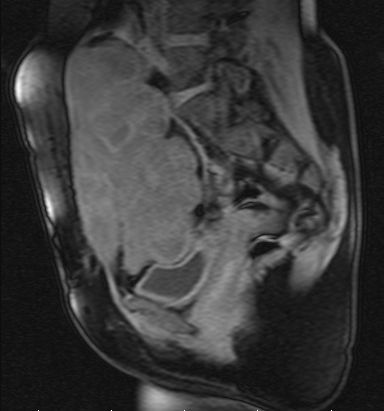

El diagnóstico por imagen es fundamental para la caracterización inicial, la planificación terapéutica y el seguimiento. La técnica de elección es la resonancia magnética (RM), por su excelente resolución de partes blandas y capacidad para definir la extensión tumoral y las relaciones con estructuras adyacentes.

Resonancia magnética (RM)

En T1, los desmoides suelen ser hipointensos o isointensos respecto al músculo. En T2, presentan señal variable: pueden ser hiperintensos (sobre todo en áreas celulares) o hipointensos (en zonas ricas en colágeno). Tras la administración de contraste, muestran realce heterogéneo. La presencia de bandas hipointensas en T2 (correspondientes a colágeno denso) es un hallazgo característico. La RM también permite evaluar la infiltración de planos musculares y la relación con paquetes neurovasculares.